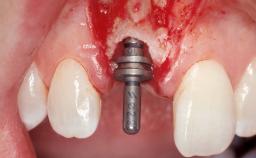

A 39-year-old male patient presented with a chief complaint of discomfort and gingival discoloration around his maxillary left central incisor. He was in good general health and was a non-smoker. His past dental history was significant because of the traumatic fracture of tooth 21 in a sporting accident at age 13. Initial dental treatment included endodontic therapy and a full-coverage restoration. The patient became symptomatic 5 years later, when structural failure of the tooth resulted in the dislodgment of the crown. Endodontic retreatment, apical surgery, and post-and-core restoration were performed.